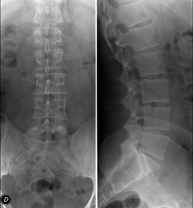

Tècnica que usa els raigs X a través de la qual s'obtenen imatges de la columna dorsal per al seu estudi. Indicacions: traumatisme, mal d'esquena. - RX Columna lumbar

Tècnica que usa els raigs X a través de la qual s'obtenen imatges de la columna lumbar per al seu estudi. Indicacions: ciàtica, traumatisme, dolor lumbar. - RX Sacre-còccix